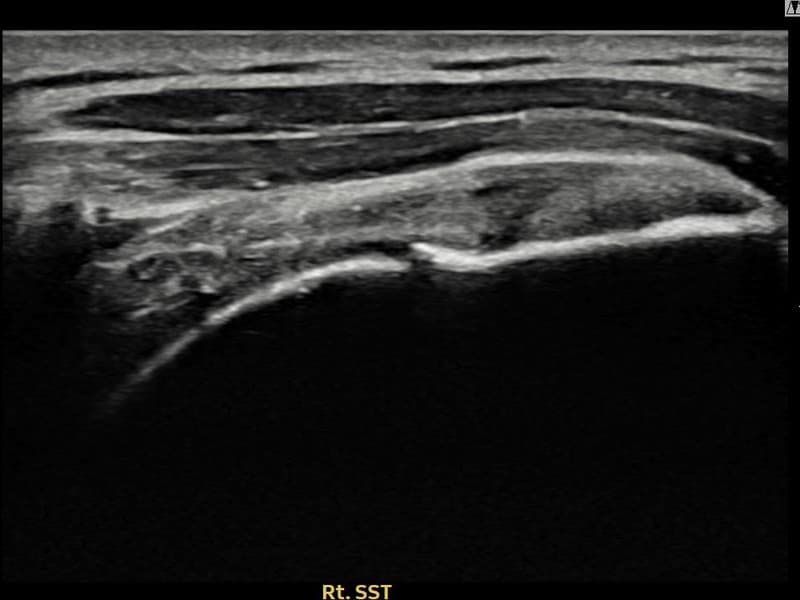

术后

术前超声确认右侧 冈上肌腱 部分撕裂 + 건내 석회화,右侧冈上肌腱回声不连续伴肌腱缺损(9mm × 4mm (肌腱厚度约38%缺损))。术后超声显示撕裂部位充满再生组织,肌腱连续性恢复,回声模式正常化。